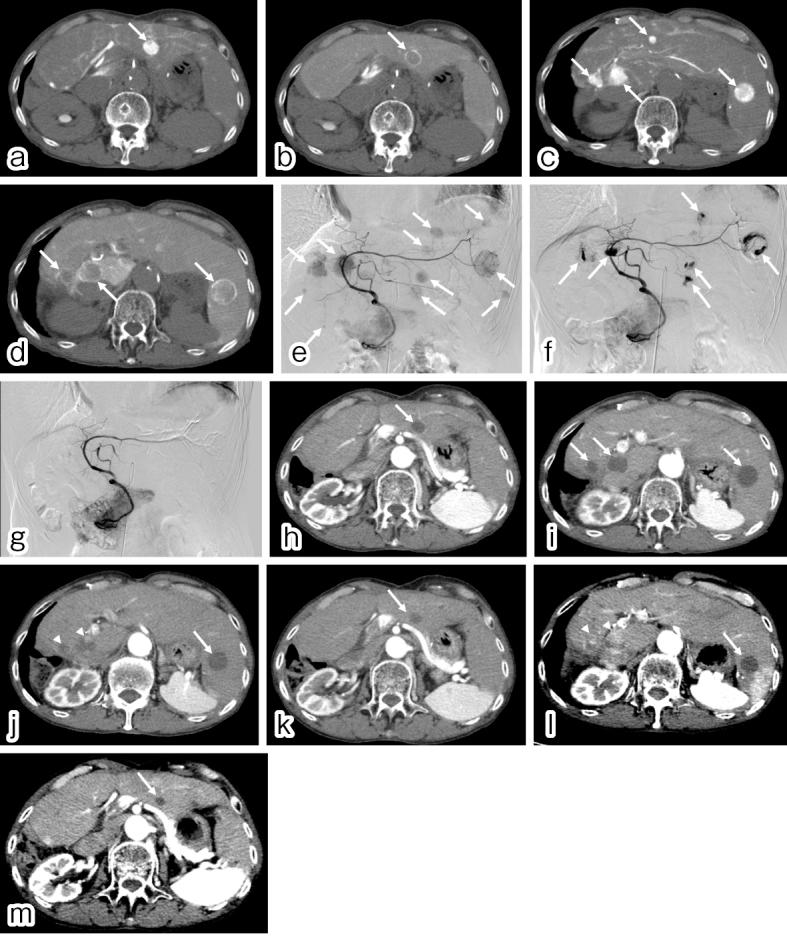

Transarterial chemoembolization is still an effective treatment option for hepatocellular carcinoma worldwide and is categorized into conventional transarterial chemoembolization with ethiodized oil transarterial chemoembolization and transarterial chemoembolization with drug-eluting spherical material transarterial chemoembolization. Several randomized controlled trials conducted in Europe have shown the equivalent efficacy of ethiodized oil transarterial chemoembolization and drug-eluting spherical material transarterial chemoembolization. However, a recent randomized controlled trials in Japan established the superiority of ethiodized oil transarterial chemoembolization in terms of complete response rates although higher liver toxicity for ethiodized oil transarterial chemoembolization. Nevertheless, the survival advantage of ethiodized oil transarterial chemoembolization is yet to be substantiated. The adverse effects of drug-eluting spherical material transarterial chemoembolization are milder than those of ethiodized oil transarterial chemoembolization, rendering drug-eluting spherical material transarterial chemoembolization an advantageous option for patients with bilobar tumors and impaired liver function/performance status. This article aims to provide an overview of these embolization techniques and a review of recent literature.

经动脉化疗栓塞术仍是全球肝细胞癌的一种有效治疗选择,可分为使用碘化油的传统经动脉化疗栓塞术以及使用载药微球的经动脉化疗栓塞术。欧洲进行的多项随机对照试验表明,碘化油经动脉化疗栓塞术和载药微球经动脉化疗栓塞术疗效相当。然而,日本最近的一项随机对照试验表明,尽管碘化油经动脉化疗栓塞术的肝毒性较高,但在完全缓解率方面具有优势。尽管如此,碘化油经动脉化疗栓塞术的生存优势尚未得到证实。载药微球经动脉化疗栓塞术的不良反应比碘化油经动脉化疗栓塞术轻,这使得载药微球经动脉化疗栓塞术成为双叶肿瘤及肝功能/体能状态受损患者的一个有利选择。本文旨在概述这些栓塞技术并回顾近期文献。